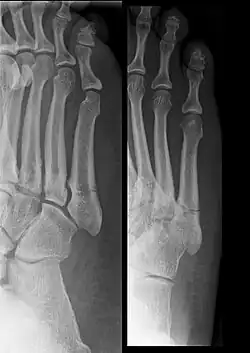

Диагноз ставится после рентгеновского исследования. Для большей точности диагноза рентген делают с разных углов и положений.